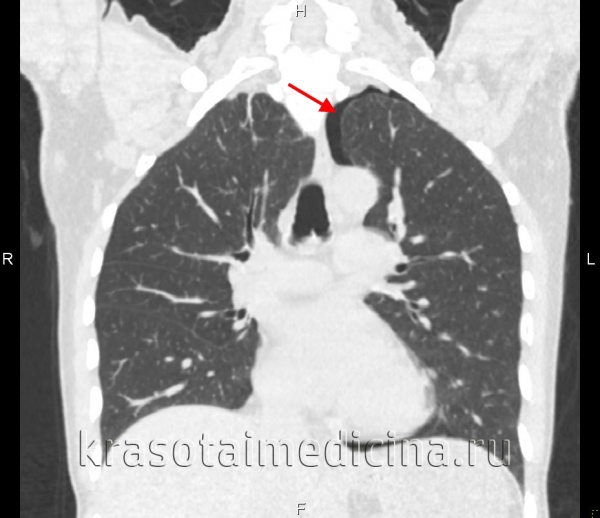

Специфические лабораторные изменения при пневмотораксе не определяются. Окончательное подтверждение диагноза происходит после проведения рентгенологического исследования. При рентгенографии легких на стороне пневмоторакса определяется зона просветления, лишенная легочного рисунка на периферии и отделенная четкой границей от спавшегося легкого; смещение органов средостения в здоровую сторону, а купола диафрагмы книзу. При поведении диагностической плевральной пункции получается воздух, давление в полости плевры колеблется в пределах нуля.

Часто оценка объема пневмоторакса используется для определения его клинического значения. Это выполняется определением расстояния от поджатого края легкого до грудной стенки в процентном отношении к общему размеру половины грудной клетки. Поскольку КТ живота стало более обычным для оценки пациентов в стабильном состоянии после тупой травмы, выяснилось, что у многих пациентов с тупой травмой есть значительные передние пневмотораксы, которые не видны при обзорной рентгенографии грудной клетки. Частота пропущенных при рентгенограмме в переднезадней проекции в положении лежа на спине пневмотораксов оценивалась в 20-35%.